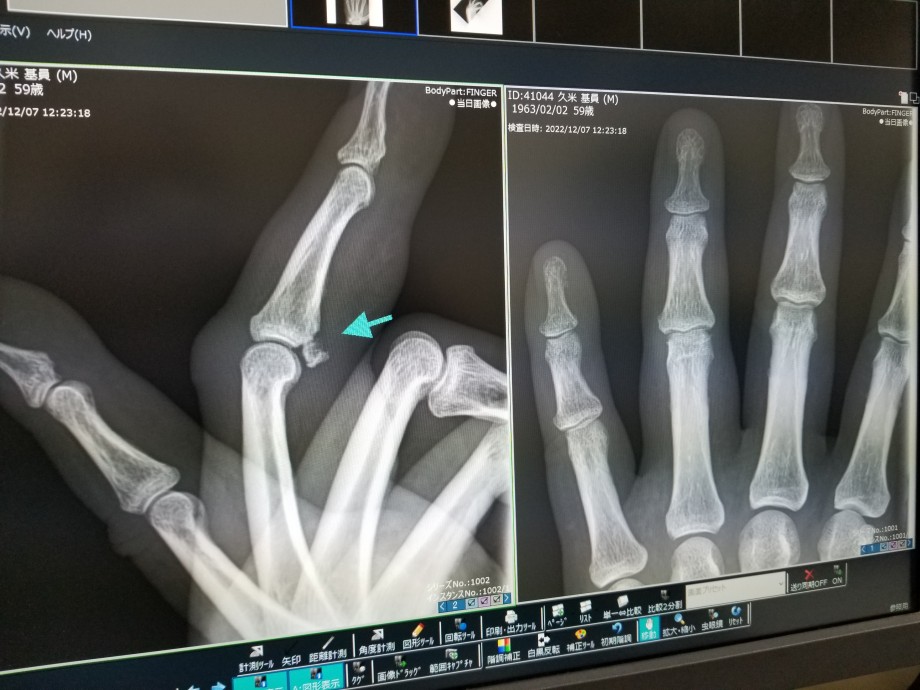

折れてますょ‼️

最初に行った整形外科は指専門で無かった為、日を改めて専門医へ

診てもらった結果、手術すれば関節の患部が硬くなり動きも悪くなる為、このままが良いだろうとの見解。